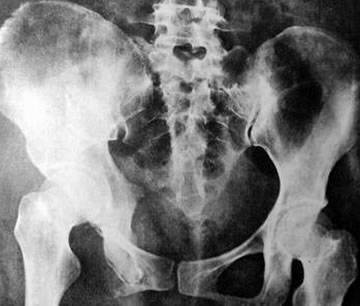

您的位置首页百科知识 尾骨骨折 Simone 发布于 2025-11-11 10:27:44 883 阅读 尾骨骨折的有关信息介绍如下:尾骨处于脊柱的最尾端,是进化退变的结构,骨折后一般没有明显的后遗症。但有些人移明显可能刺激直肠,另外有很少部分人尾骨骨折后会出现局部顽固性的疼痛,除了这些一般不会有什么后遗症。想要了解更多“尾骨骨折”的信息,请点击:尾骨骨折百科